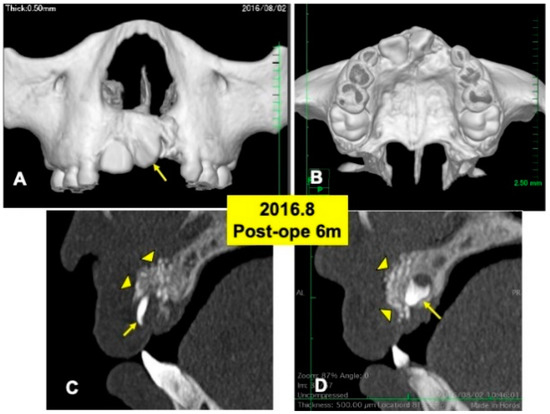

Gross View and Radiographic Evaluation after Surgery